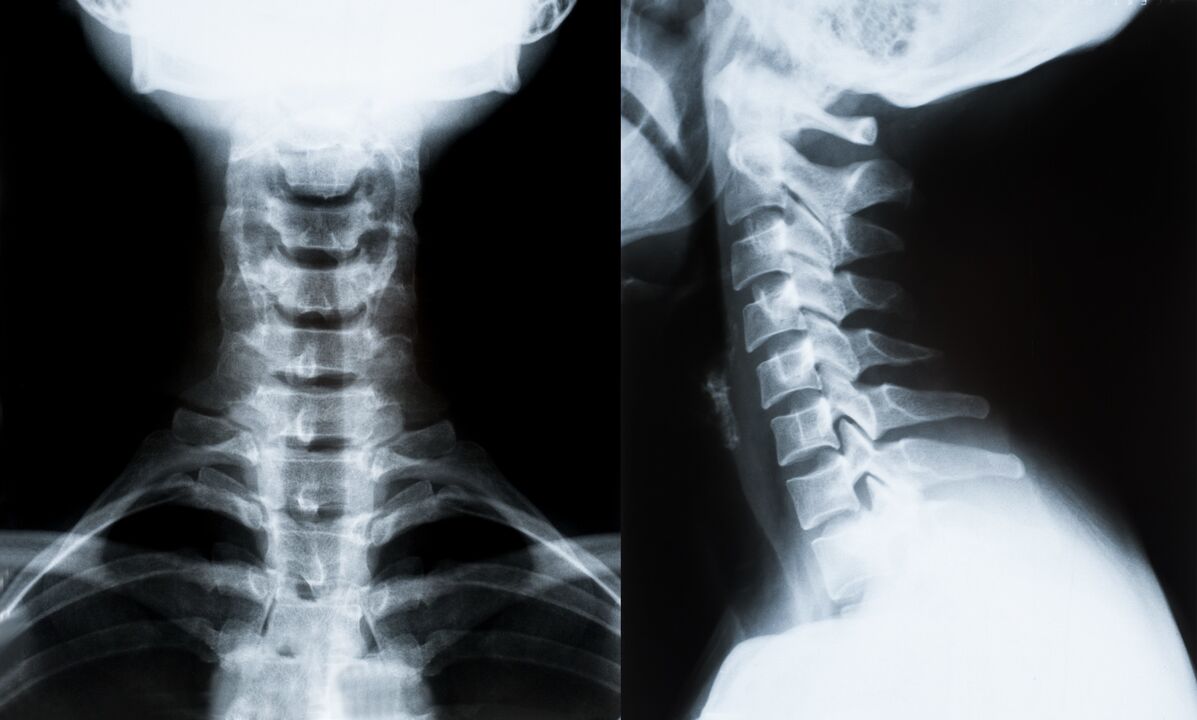

I principali metodi per diagnosticare e determinare ulteriormente il trattamento dell'osteocondrosi del rachide cervicale:

- Roentgen. Il metodo diagnostico meno efficace, ma tradizionale.

- La risonanza magnetica è il metodo diagnostico più efficace. Con questo tipo di esame del paziente sono visibili tutte le strutture necessarie.

- Se è necessario misurare i cambiamenti, viene utilizzata la tomografia computerizzata. Determina la presenza di ernie e altre cose.

- L'ultimo metodo è l'esame ecografico duplex. Questo metodo di ricerca determina la velocità del flusso sanguigno nelle arterie.

È impossibile determinare con precisione una malattia spinale a casa.